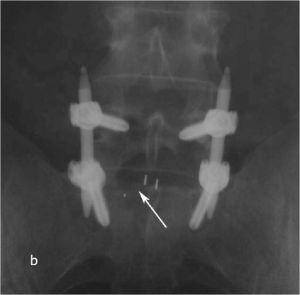

Пациенту выполнено оперативное лечение: удаление секвестрированной парамедианной грыжи мп диска L5-S1 слева из минидоступа, миниинвазивная транспедикулярная фиксация L5-S1 титановой конструкцией.

При контрольной рентгенограмме отмечено правильное положение транспедикулярной системы и кейджа на уровне L5-S1 позвонков. (Рис.9)

Рис. 9 a,b. Ренгенограмма поясничного отдела позвоночника в боковой (a) и прямой (b) проекции. Транспедикулярная фиксация L5-S1 позвонков титановой конструкцией канюлированными винтами, межтеловая фиксация позвонков кейджем из PEEK-керамики. Стрелкой указано положение ренген–негативного кейджа, видны титановые метки кейджа.